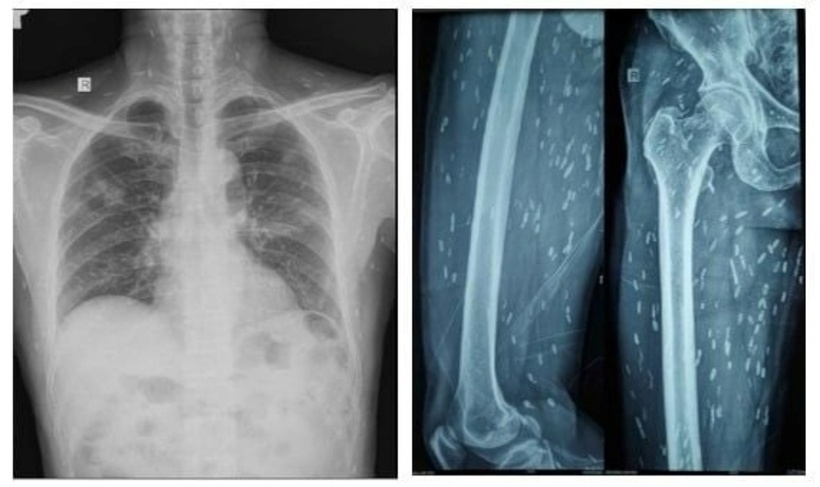

Bệnh nhân được chụp Xquang xương đùi, CT-scan ngực để tầm soát tổn thương ở cơ quan khác, phát hiện vô số nang sán dải còn sống hoặc đã bị hóa vôi “ẩn nấp” trong não, nhu mô phổi, và trong da, cơ trên toàn bộ cơ thể người bệnh.

Nang sán chi chít cơ thể người đàn ông. Ảnh: BVCC.

Trường hợp này được chẩn đoán viêm não do nang sán dải lợn và nhiễm nang sán dải ở đa cơ quan, nổi bật nhất là ở não, mô dưới da và ở cơ. Người bệnh nhanh chóng được điều trị bằng thuốc chống ký sinh trùng, chống viêm, phòng ngừa co giật cùng với chăm sóc tích cực. May mắn, bệnh nhân hồi phục tốt sau quá trình điều trị và được xuất viện